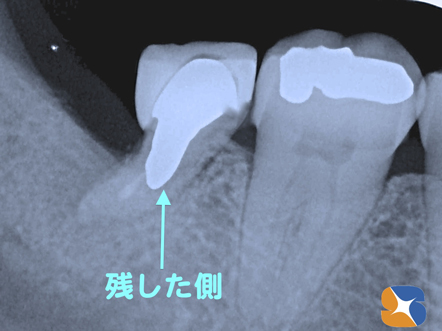

奥歯を二つに割って、残す側と抜く側に分ける 【before】奥歯に入ったヒビが原因で、歯茎にデキモノが出る歯のレントゲン写真です。

半分残した歯の根に金属の補強芯とセラミックの被せを装着 【after】 歯を2分割して、状態が良い手前の半分を残して、金属の補強芯を接続して、自作のセラミックの被せ物を装着したところのレントゲン写真です。